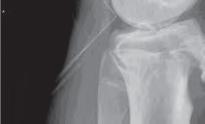

Podział złamań kości rosnących, tzw. złamań nasadowych: A – schematyczne przedstawienie klasyfikacji złamań; B – SH I (RTG, widok z przodu i z boku); C – SH II (RTG, widok z przodu i z boku); D – SH II (TK, widok z boku); E – SH III (RTG, widok z przodu i z boku); F – SH IV (RTG, widok z przodu i z boku); G – SH V (RTG, widok z przodu i z boku).

Rozpoznanie

Objawy złamania to silny ból uniemożliwiający stanie i chodzenie, zniekształcenie obrysów stawu kolanowego przez krwiak i różnego stopnia przemieszczenie nasady kości piszczelowej. Należy dokładnie zbadać stan ukrwienia i unaczynienia kończyny pod kątem objawów uszkodzenia tętnicy podkolanowej i nerwu strzałkowego. Trzeba ocenić bolesność uciskową oraz napięcie w przedziałach powięziowych podudzia: przednim, bocznym, tylnym powierzchownym i tylnym głębokim. U pacjentów z podejrzeniem wzmożonego ciśnienia wewnątrzprzedziałowego należy wielokrotnie powtarzać badanie ukrwienia i unerwienia kończyny, a w razie zaistnienia wskazań wykonać bezpośredni pomiar ciśnienia w przedziałach. Powinno się zawsze podejrzewać możliwość uszkodzeń więzadłowych współistniejących ze złamaniem. Badania obrazowe to RTG w pozycji AP, bocznej i skośnej. Wykonanie badania TK może być konieczne w celu pełnej oceny rozległości

złamania. W przypadku podejrzenia uszkodzenia tętnicy podkolanowej należy wykonać angio-TK lub arteriografię.

Leczenie złamania bliższej nasady piszczeli w przypadku uszkodzenia typu 1 i 2 według Saltera i Harrisa leczymy nieoperacyjnie. Należy wykonać zamkniętą repozycję i unieruchomić w opatrunku gipsowym udowym w zgięciu kolana 30–60°, zapewniającym najlepszą stabilność odłamów. Okres unieruchomienia wynosi od 6 do 7 tygodni. Po tym czasie usuwamy gips i zaczynamy ćwiczenia zwiększające zakres ruchomości stawu kolanowego oraz wzmacniające siłę mięśnia czworogłowego. Ważne jest, by prowadzić częste kontrole stanu ukrwienia i unaczynienia oraz kontrole radiologiczne w celu wykrycia ewentualnych przemieszczeń odłamów. Złamania pierwotnie niestabilne lub wtórnie przemieszczone wymagają zamkniętej repozycji stabilizacji drutami K. Typ 3 i 4

Złamania rzepki i podudzia

złamania według Saltera i Harrisa wymaga leczenia operacyjnego w postaci otwartej repozycji i stabilizacji śrubami. Należy unikać krzyżowania metalu zespalającego z chrząstką wzrostową. Kończynę zgiętą w kolanie do 30° unieruchamia się w gipsie udowym na okres 6–8 tygodni. Po tym czasie rozpoczynamy ćwiczenia czynne poprawiające zakres ruchomości kończyny.